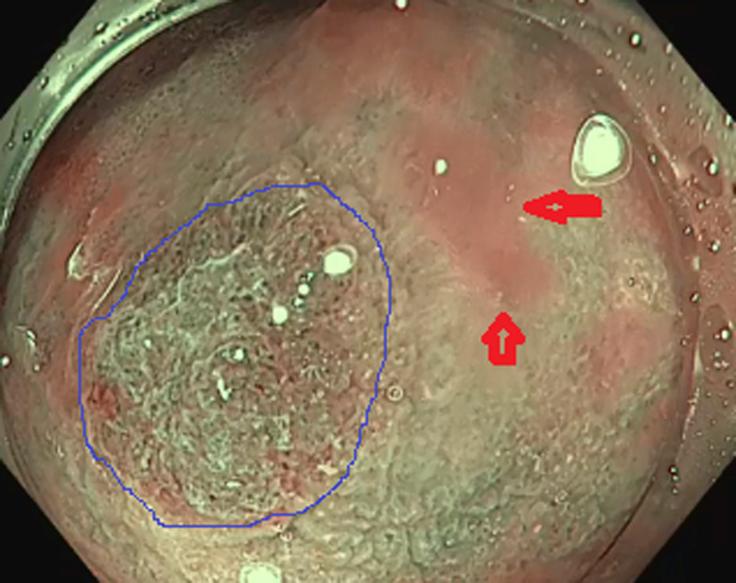

Endoscopic recognition of the sessile serrated polyp to cancer sequence.

VideoGIE. 2017 May 10;2(7):185-187. doi: 10.1016/j.vgie.2017.04.004. eCollection 2017 Jul.